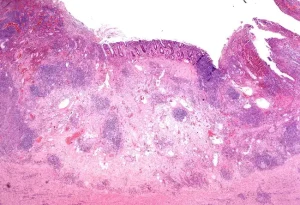

Endoskopik Testler: Kolonoskopi veya endoskopi gibi testler, bağırsaklarda iltihap olup olmadığını gözlemlemek için kullanılır.

Biyopsi: Doktor, bağırsaklardan örnek alarak iltihaplanma ve hücre değişikliklerini inceleyebilir.